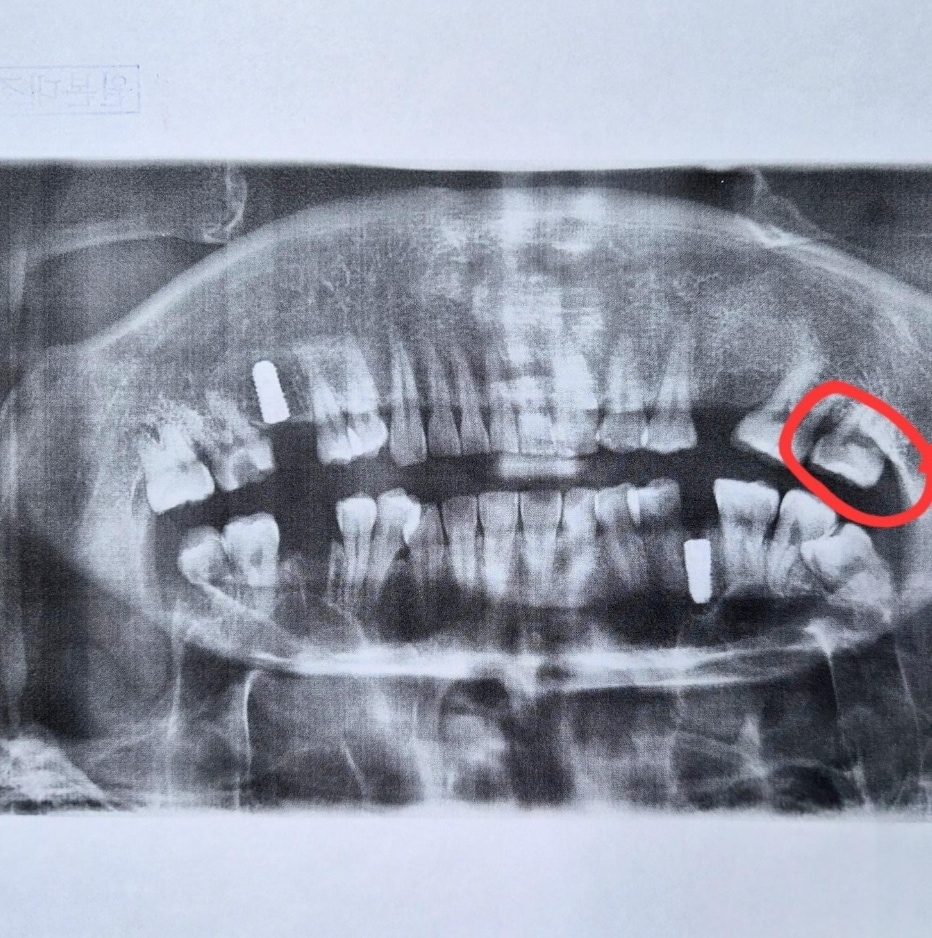

A 씨는 "제가 뇌 장애가 있어서 인지가 조금 느린 편인데 병원에서 나와 곰곰이 생각해 보니 잘못됐다는 생각이 들었다"며 "멀쩡히 쓰던 치아였고 사진을 봐도 문제가 없어 보이는데 반을 깎아버렸다"고 말했다.

A 씨는 "사진을 가리키며 저게 어떻게 사랑니냐고 물었는데도 계속 맞다고 했다"며 "설사 사랑니라 하더라도 실수로 남의 치아를 발치하게 만들어놓고 이건 아닌 것 같다"고 주장했다.

반면 "사진상 사랑니가 맞다", "충치가 심해 발치 소견이 나올 수 있다", "치과의 설명이 미흡한 점은 아쉽지만 결국 뽑게 될 치아였을 가능성이 크다"는 반응을 보이기도 했다.